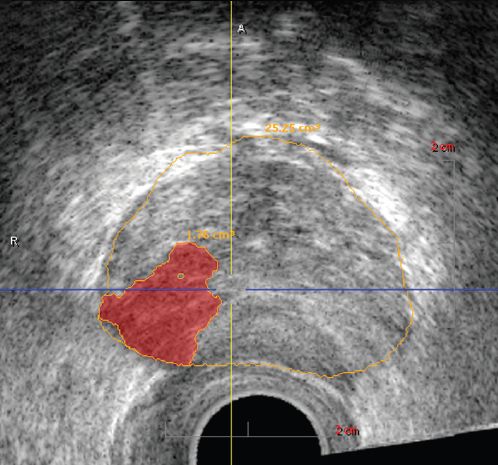

Šodien pasaulē atzīmē pretvēža dienu, un īsi pirms šīs dienas Rīgas 1. slimnīcā pirmoreiz Latvijā izmēģināta jauna trīs dimensiju histoskenēšanas tehnoloģija – jaunā aparatūra izmeklējuma laikā urologam ļauj novērtēt prostatas stāvokli, precīzi nosakot no normāliem audiem atšķirīgu audu atrašanās vietu, kas liecina par vēzi. Ultraskaņas procedūras laikā tiek uzņemts augstas izšķirtspējas trīs dimensiju prostatas attēls, kurā no normāliem audiem atšķirīgie audi tiek iekrāsoti, tādējādi atvieglojot prostatas vēža diagnostiku. Turklāt aparatūra palielina biopsijas precizitāti, radot iespēju veikt tēmētu izmainīto audu paraugu paņemšanu un samazinot nelietderīgu biopsiju skaitu.

«Līdz šim urologu iespējas efektīvi diagnosticēt vēzi bija ierobežotas,» norāda urologs Atis Karulis. Prostatas vēzis ir plaši izplatīta slimība ne tikai Latvijā, bet arī pasaulē, taču viens no lielākajiem šķēršļiem ir iespēja precīzi noteikt tā atrašanās vietu. A. Karulis atzīst, ka, protams, mūsdienās ir pieejami vairāki izmeklējumu veidi, kas sniedz svarīgu informāciju, taču neviens no tiem nedeva iespēju pilnīgi precīzi diagnosticēt prostatas izmainīto audu atrašanās vietu. Taču, izmantojot jauno aparatūru, tiek panākta prostatas vēža diagnostikas kvalitātes uzlabošana. Jaunā tehnoloģija radikāli mainījusi veidu, kā prostatas vēzis tiek diagnosticēts.